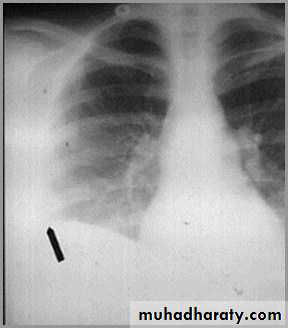

postpnemonectomy

The hemithorax eventually fibroses and becomes opaqueClues: There is frequently a resected fifth rib and/or surgical clips

quiz